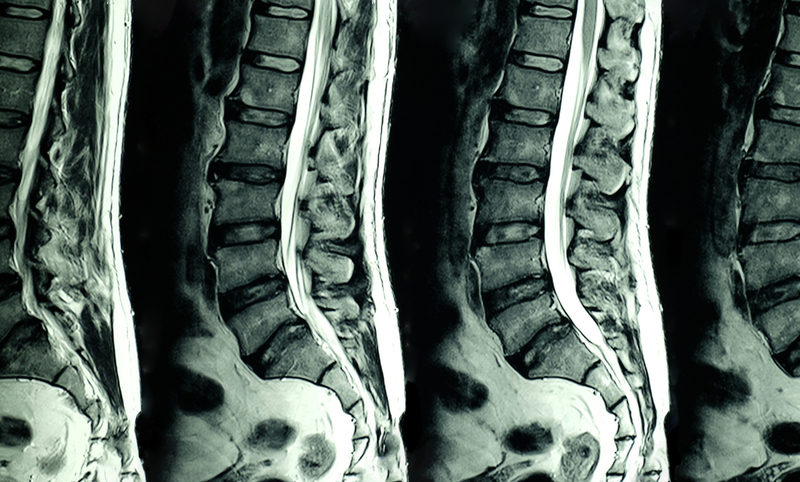

The girl was suffering from spinal arteriovenous malformation (AVM) in which there is an abnormal tangle of blood vessels in or near the spinal cord. The disease can permanently damage the spinal cord if not treated properly and on time, the hospital said in a statement on September 22.

The patient's repeated MRI C-Spine revealed that she had longitudinally extensive hematomyelia (blood in spinal cord) with central cord lesion (C7-D1). Through her DSA angiography reports, the doctors discovered that she had spinal AVM along with C7-D1 as the cause of hematomyelia. "We performed DSA with Embolisation of spinal AVM along with C7-D1 on her. She responded well to the treatment and was discharged within few days after the surgery," Renjen said.